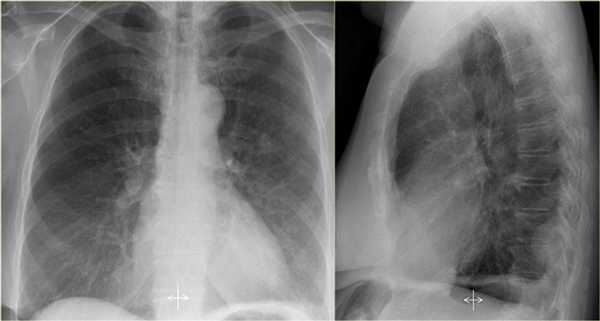

На рентгенограмме представлен тотальный коллапс верхней доли левого легкого. Обратите внимание на высокое стояние левого корня легкого. Спавшаяся верхняя доля левого легкого расположено позади грудины. В данном случае компенсаторная гипервентиляция нижней доли левого легкого повлияло на то, что позиция диафрагмы и средостения в норме.

Ателектаз нижней доли левого легкого

На рентгенограмме визуализируются изменения трехгранной формы высокой плотности, расположенные позади тени сердца, что хорошо выявляется на боковом снимке. На боковом снимке при оценке контура диафрагмы спереди назад определяется все менее четко. Исходя из названия раздела напрашивается диагноз — ателектаз нижней доли левого легкого. В норме прозрачность легкого внизу выше, а в нашем случае наоборот (синяя стрелка).